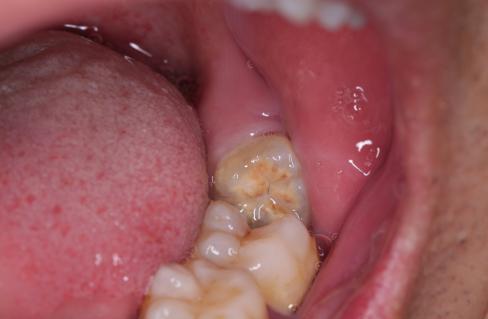

前倾阻生智齿,它的牙冠向前倾倒,直抵邻牙颈部,无论在口腔内还是X线片上都很直观,在形态上,跟警察跪压在黑人颈部非常相似,而且造成的后果也基本相同。

前倾智齿与邻牙形成一个敞开的间隙,经常会残留食物残渣,并且属于刷牙难以清理的死角,因此在邻牙邻面极易沉积菌斑,时间稍长即可形成邻面龋,龋损一旦攻破薄弱的牙骨质进入牙本质,邻牙即进入快速崩解毁灭期,于是产生临床上常见的“拔一送一”现象。

智齿顶着邻牙颈部的状况,是阻生智齿中产生危害最多的一种,临床上还有很多阻生智齿类型,前倾智齿冠部如果继续下倾,抵住牙颈部以下甚至牙根部位,乃至智齿全部埋伏在下颌骨内,那么产生危害不可预见,远不比肉眼可见的前倾智齿那么普遍。前倾智齿邻牙颈部菌斑导致龋坏是极大概率事件,而骨埋伏智齿只是可能形成“含牙囊肿”,或者因向前的生长潜力导致邻牙根破坏,它不存在菌斑因素,所以破坏没有那么直接,只能说风险客观存在,并且没有任何医生可以预测。